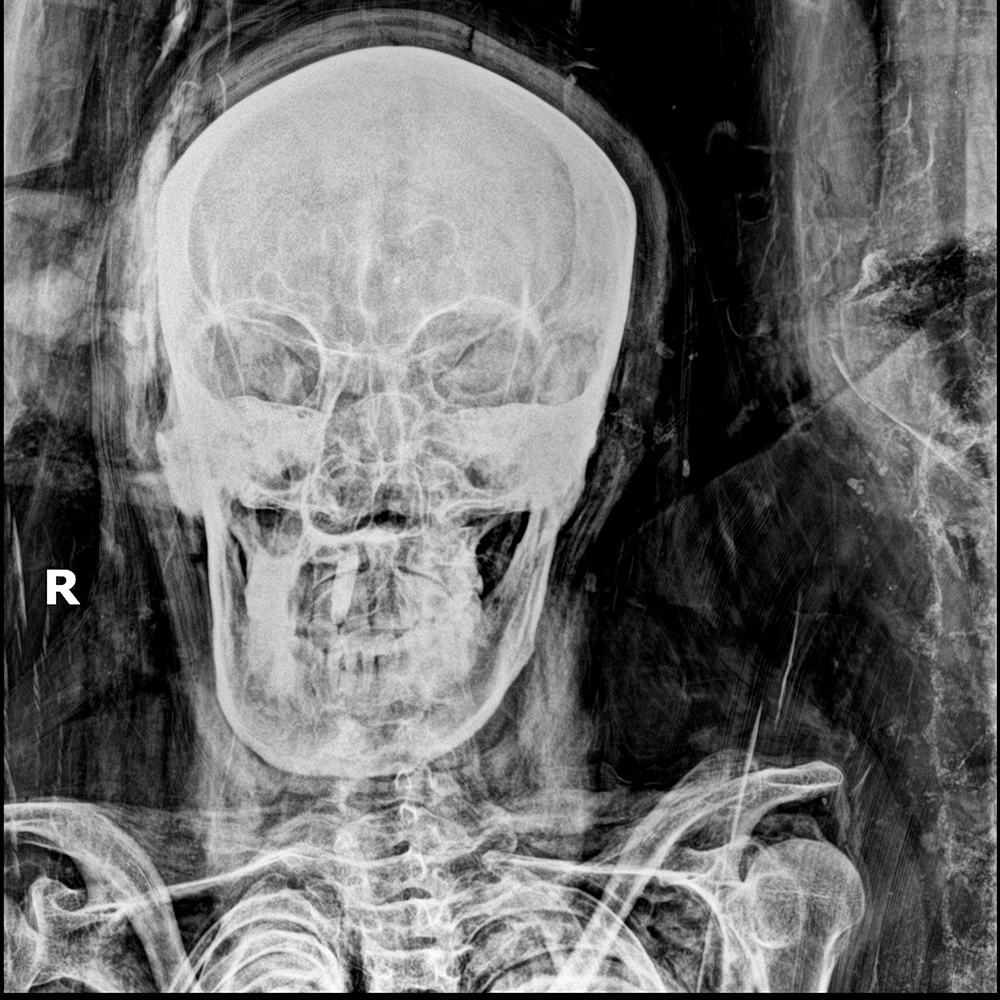

Moderately/severely symptomatic patients: CXR is often negative early, only to turn positive subsequently. The most characteristic findings are basilar and peripheral ground-glass opacities (GGOs) (Fig. 1).